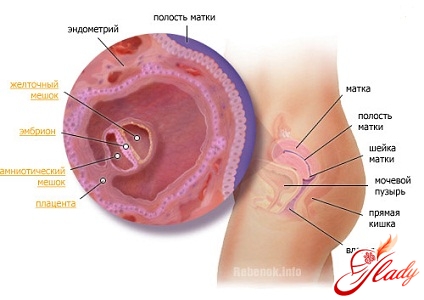

Когда наступает беременность 4 неделя – это время преобразования плодного яйца в эмбрион, который напоминает плоский диск. Эмбрион состоит из трех зародышевых листков, которые и служат началом для формирования тканей и органов ребенка. Внутренний слой называется эндодермой, из него в дальнейшем развиваются печень, легкие, пищеварительная система, почки и остальные внутренние органы. Беременность 4 неделя признаки ее проявляются внутри организма будущей матери: второй слой – мезодерма служит основой для мышечной и кровеносной системы, из мезодермы формируются сердце и почки. А эктодерма – внешний слой дает начало коже, волосам, нервной системе и зубной эмали. Чуть позже клетки листков занимают свои места, и начинается формирование головки плода.

Беременность 4 неделя симптомы: Момент закладки всех органов чрезвычайно важен, в этот период закладываются и внезародышевые органы – хорион, амнион и желточный мешок. Из хориона развивается плацента, а из амниона – плодный пузырь. Внезародышевые органы при диагнозе беременность 4 неделя УЗИ обследованию еще практически недоступны, хотя врач уже сможет установить факт беременности.